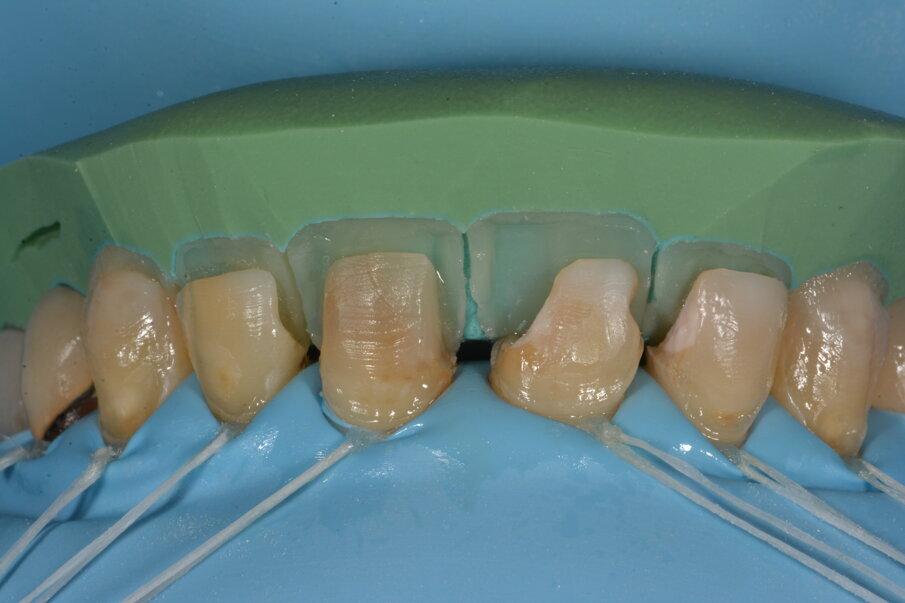

Om de interdentale ruimtes op te bouwen maken we gebruik van een rechtopstaande niervormige matrix. Door de convexiteit van de matrix naar buccaal te plaatsen hebben we al een referentie om het buccale vlak te modelleren. Het wit-roze materiaal dicht bij de pulpa is de 3M Filtek Universal Restorave Pink Opaquer, die het verkleurde dentine zal maskeren om zo een uniformere kleur te kunnen verkrijgen.

De resterende holte werd via buccaal verder in laagjes opgevuld.